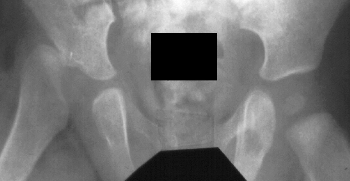

A 6 week old boy was in breech position and delivered by C-section. He is the first child for this 38 year old mother. At 6 weeks of age a dislocated hip was noted. He was placed in a Pavlik harness but this treatment was unsuccessful. Closed reduction was performed, but the hip redislocated.

If the harness fails to reduce the hip, doing a closed reduction under anesthesia with spica cast immobilization is the next treatment to try.

The hip probably dislocated because there was not enough hip abduction in the cast .

A Computerized Tomographic scan is the best method to be certain that a closed reduced hip is in fact reduced.